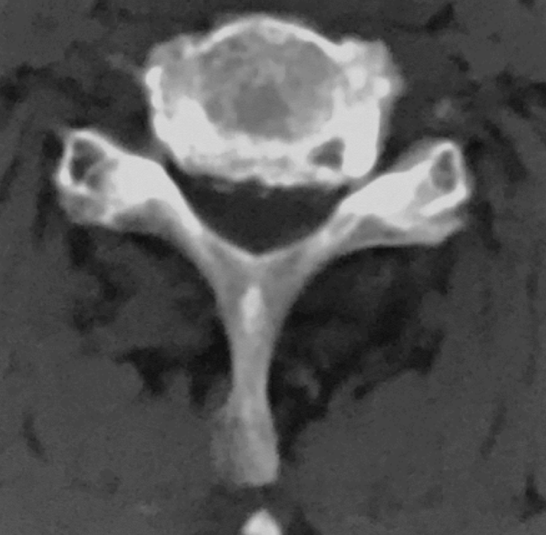

CT:C5-6

骨窗

行颈前路减压植骨融合内固定术,由于患者钩椎关节增生严重,术中应用超声骨刀对对骨赘进行切除。

超声骨刀辅助下切除患者左侧增生的钩突,手术过程顺利